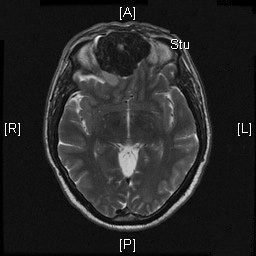

Radiologic Images of the Case: CT scan demonstrated a large midline mixed density mass with fat density that occupies the ethmoid sinus with extension through the cribiform plate into the inferior portion of the anterior cranial fossa. The mass is 5.1 x 3.2 cm in greatest dimension (Panel A). Bone windows of CT scan demonstrated bone expansion suggestive of remodeling (Panel B). On MRI, spoiled gradient recalled (SPGR ) post contrast images showing mass is either avidly enhancing or bright on T1 precontrast. (Panel C). The mass hypointense signal intensity compared to brain parenchyma with surrounding areas of increased signal (suggestive of entrapped mucus) on T2 weighted images (Panel D and E).